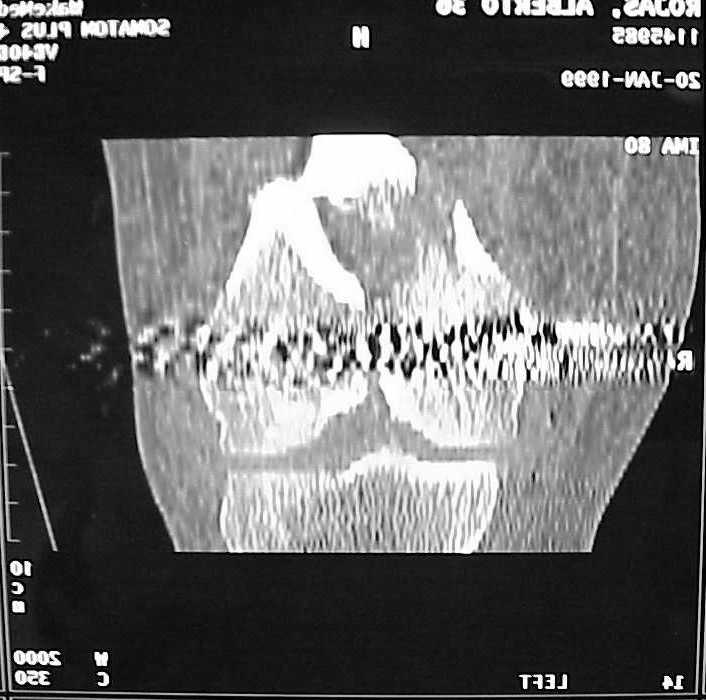

Мы пошли на операцию с планом попытаться сделать закрытый интрамедулярный, а не получится - сделать аппаратом. Посчитали, что получилось, хотя на еженедельной конференции ожидаются некоторые проблемы с объяснениями ;-)

Насчет стабильности для ранней нагрузки, конечно, сомнительно, но при таком повреждении ранняя нагрузка противопоказана в любом случае. Для ранних движений Должно хватить. Снимки в следующем сообщении.

воспользовались для репозиции, см. приложение.